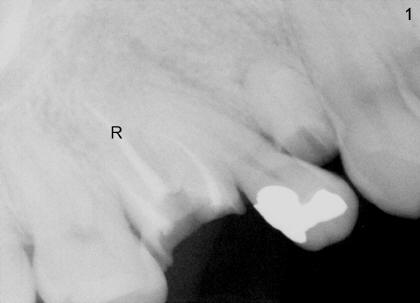

1. A post is needed when the tooth has a large defect and has finished root canal therapy (R in Fig.1).  There are two types of post: prefabricated and cast (one and two appointments, for small and large decays, respectively).  A post space is created in the largest canal of the tooth (arrowheads in Fig.2).  Either a prefabricated post is inserted into the post space or a plastic pattern is made to fit the space.  The outside portion of the pattern is prepared (trimmed) to become part of the tooth structure.  The plastic pattern is sent to lab to make a cast post (P) and core (C, Fig.3), which is inserted (Fig.4) into the post space.  Finally a crown is cemented (Cr in Fig.5)

3. PA device is needed for both appointments: to confirm length of post space to be created (Fig.2) and seating of cast post (Fig.4)